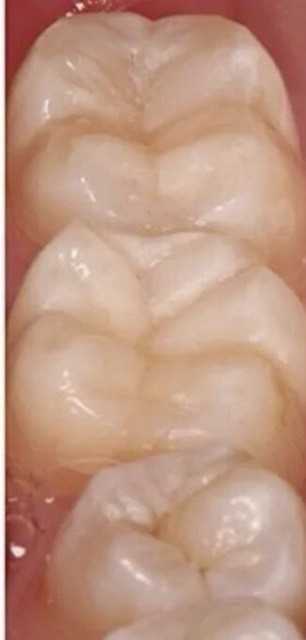

19 работ в портфолио

Щербакова (Полякова) Анна Сергеевна принимает в сети семейных стоматологических клиник ИЛАТАН в Москве. Стаж 11 лет. Специализируется на детской стоматологии и эндодонтическом лечении, по которым клиника оказывает 14 услуг. Имеет 19 работ до/после в портфолио. Квалификация специалиста подтверждена 21 лицензиями, сертификатами и наградами, а опыт 13 отзывами пациентов, из которых 13 положительные. Для уточнения дополнительной информации о специалисте или записи на прием можно позвонить по телефону